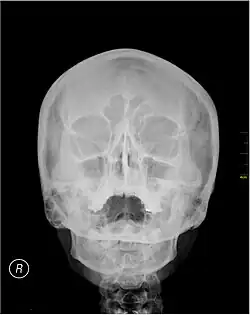

Waters' view

Waters' view (also known as the occipitomental view or parietoacanthial projection) is a radiographic view of the skull. It is commonly used to get a better view of the maxillary sinuses. An x-ray beam is angled at 45° to the orbitomeatal line. The rays pass from behind the head and are perpendicular to the radiographic plate. Another variation of the waters places the orbitomeatal line at a 37° angle to the image receptor. It is named after the American radiologist Charles Alexander Waters.

Waters' view can be used to best visualise a number of structures in the skull.

- Maxillary sinuses.

- Frontal sinuses, seen with an oblique view.

- Ethmoidal cells.

- Sphenoid sinus, seen through the open mouth.

- Odontoid process, where if it is just below the mentum, it confirms adequate extension of the head.

The Waters' view may not show the frontal sinus in detail.[1]